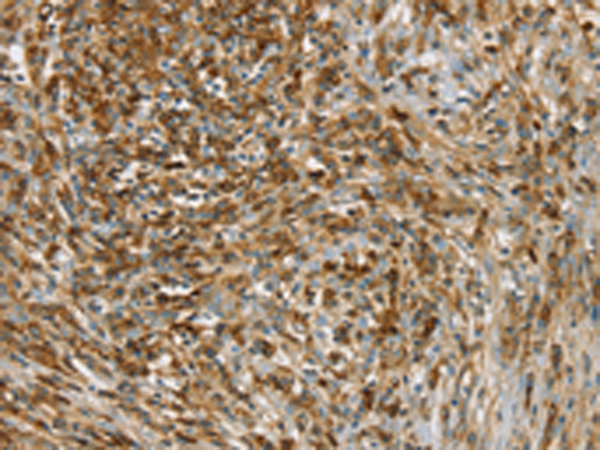

IHC positive control: |

Human cervical cancer |

IHC Recommend dilution: |

25-100 |